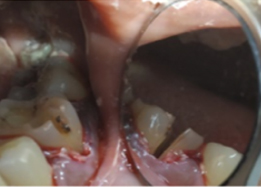

Post-OP Clinical View